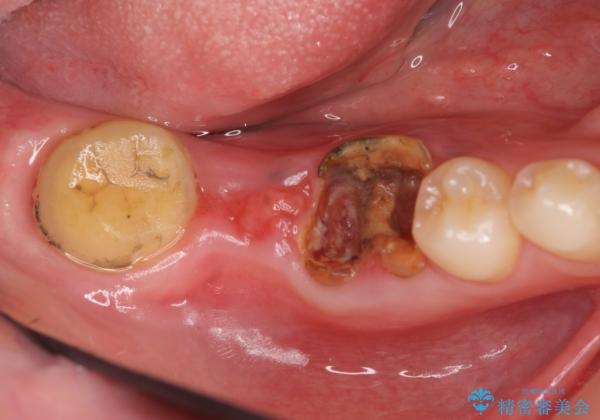

右下は虫歯がひどく、抜歯が必要でした。また、右下の一番奥の歯は親知らずのため使うことができない状態でした。